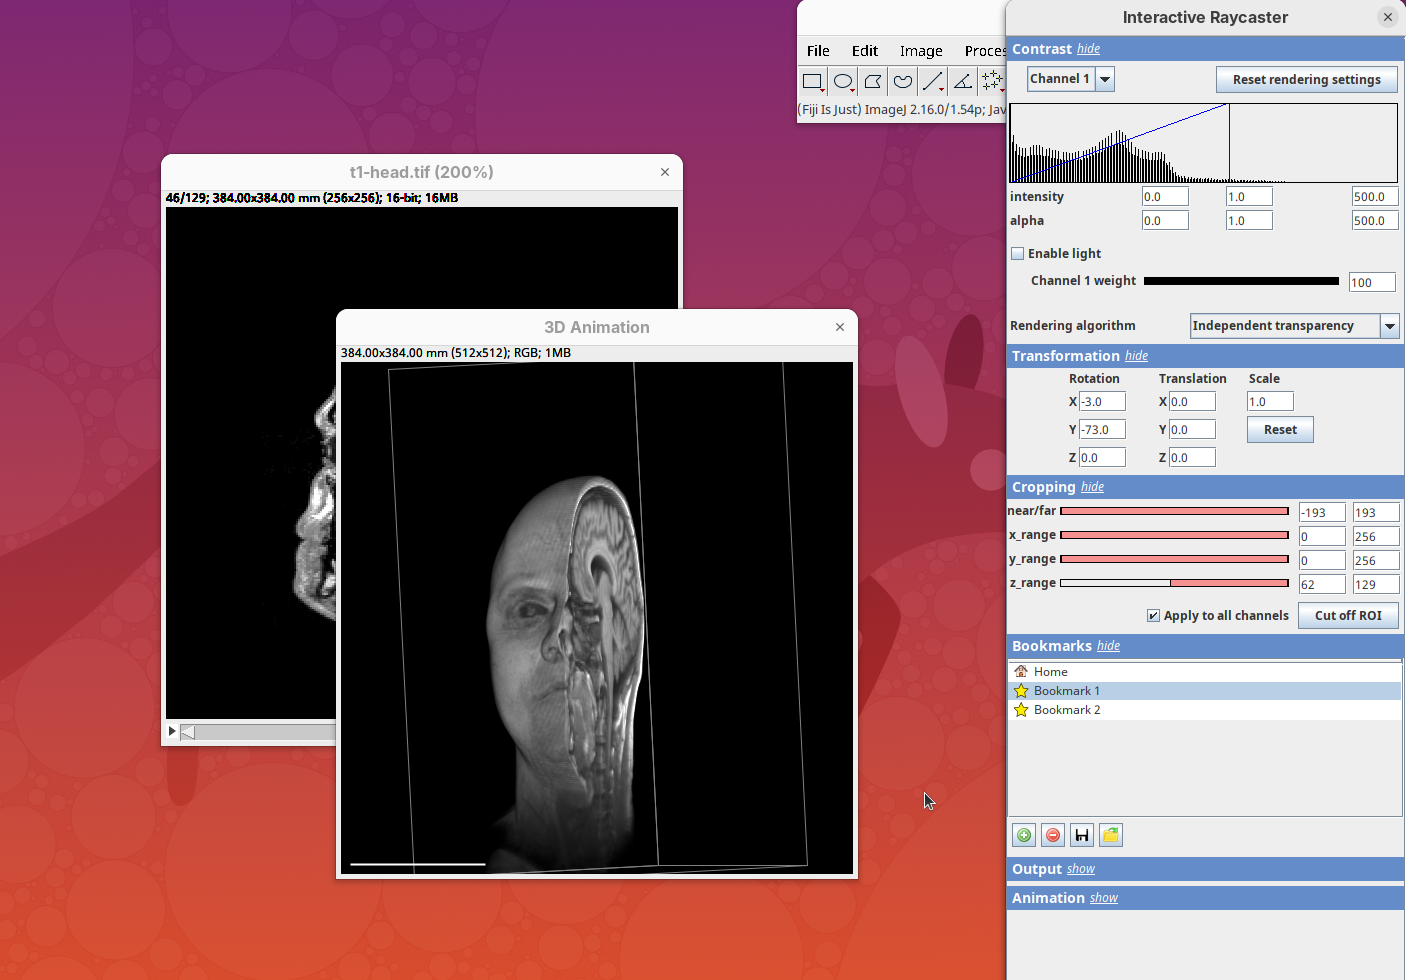

The transformation menu has controls for rotating, translating, and scaling the sample. We can either add values or manually interact with the 3D Animation window to reorient the sample. Let’s try the latter.

- Left-click on the head and move it around.

That’s a great way to see your sample from different angles. And note that the values in the Transformation panel get updated every time you move the sample interactively. In this way you can roughly position the sample and then check and update the precise values for the target transformation.

- Press

Resetand change theRotation Yto180to look at the right side of the head.

Cropping

Another useful 3Dscript option is the ability to crop the bounding box to show the inside of the sample. We can do it in the XYZ directions or in the near/far axis, defined from the user point of view.

- Set the Z range minimum value to

60(you can also drag the slider) to slice the sample through the Z axis.

- Now rotate the sample to see the cropped region from other angles.

- Set the Y range

minto125and rotate around.

- Finally, reset the position and cropping parameters and set the Near/Far minimum to

0and move the sample around to see the dynamic reslice of the sample with this cropping parameter.

- Reset transformations and cropping parameters.

Bookmark

3Dscript allows you to bookmark a view for later inspection. Add the current Contrast, Transformation, and Cropping parameters to the bookmark.

- For that, simply click on the green icon.